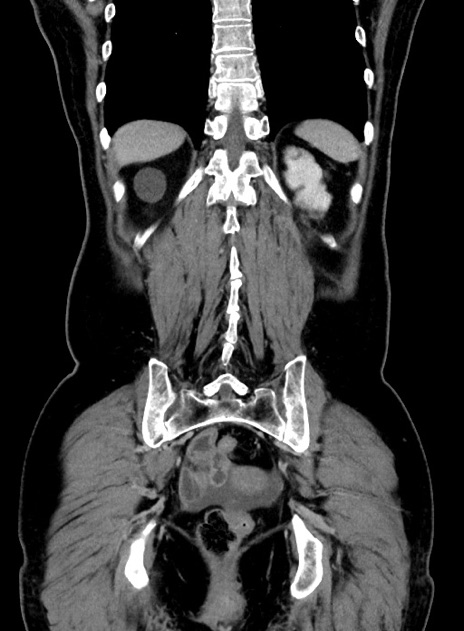

症例9(冠状断像)

症例

【症例】 60歳代女性

【主訴】むかつき、みぞおちの痛み

【現病歴】3日前よりむかつきがあり、食事がとれない。

【既往歴】糖尿病

【身体所見】発熱なし、心窩部圧痛軽度あるも、腹膜刺激症状なし。

【データ】WBC 7400、CRP 1.92